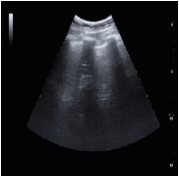

Assinale a opção que apresenta a imagem de ultrassonografia pulmonar compatível com a descrição do quadro acima.